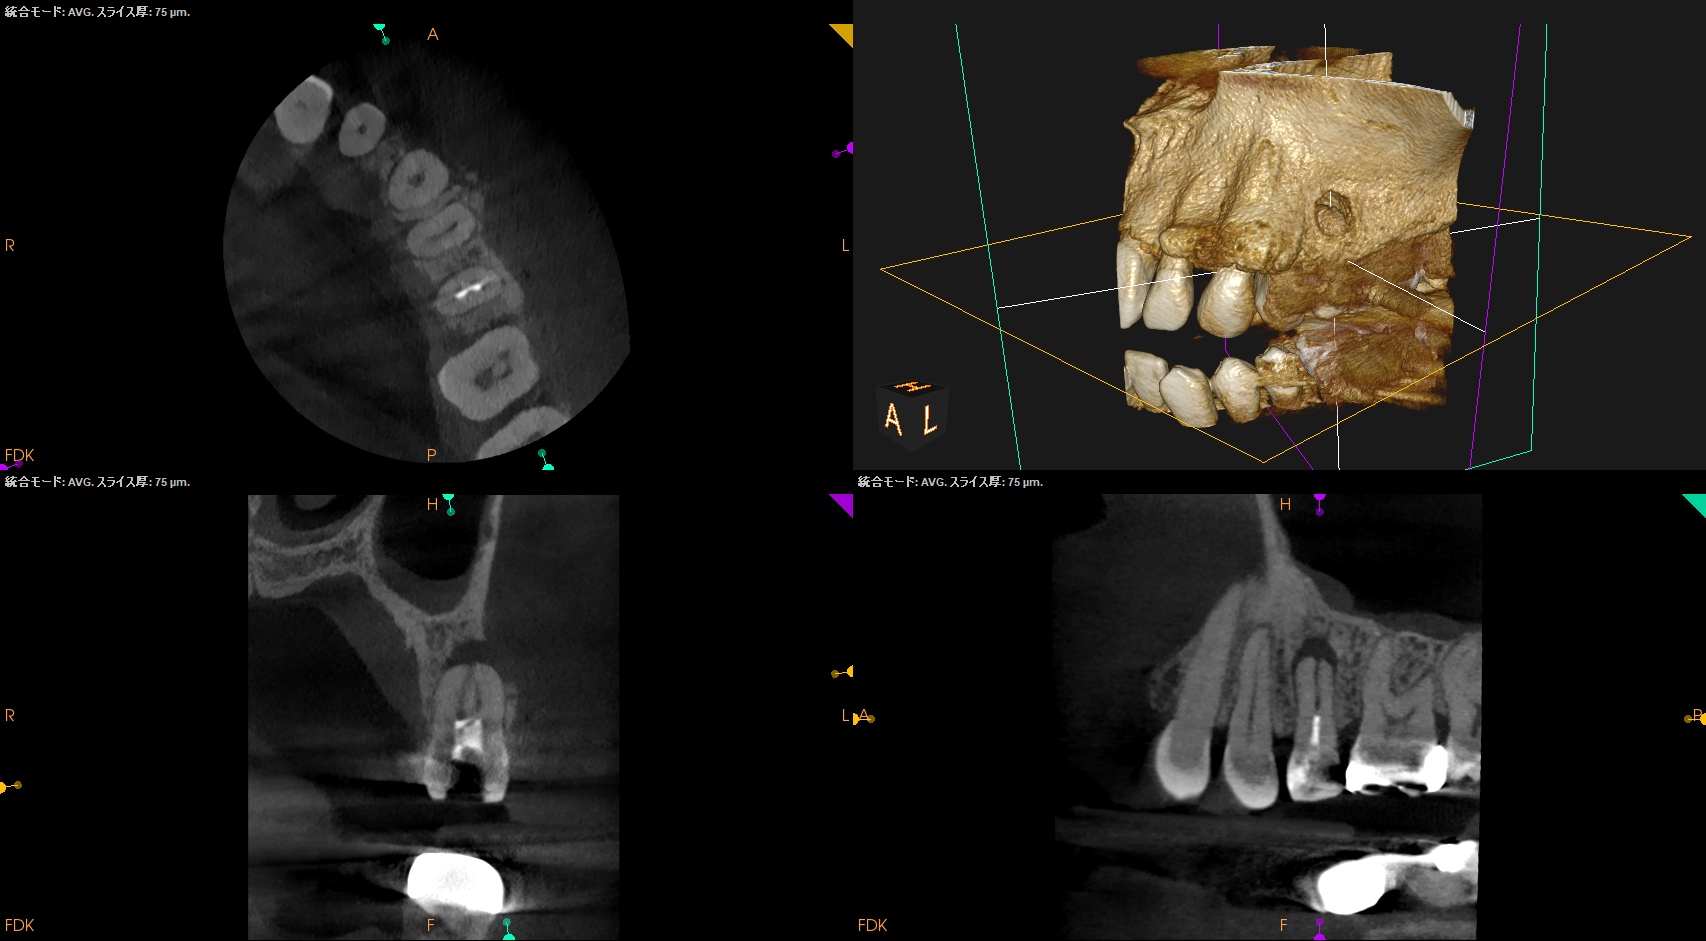

またCBCTを撮影すると、

B

P

歯槽骨は溶けて#13のApexが口腔内に露出しかけている。

これが圧痛の原因になるのは間違いないだろう。

が、Sinus tractがないのであればこの歯の治療の成功率は

86%

de Chevigny 2008 Treatment outcome in endodontics: the Toronto study–phase 4: initial treatment

である

ということが処置前にわかる。